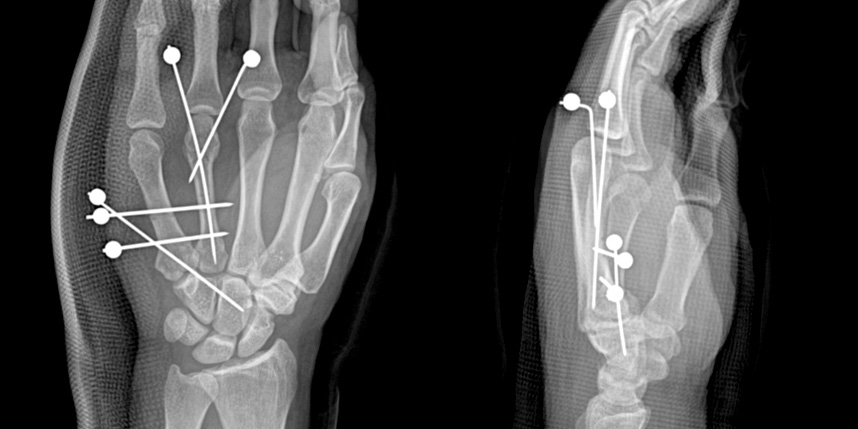

손가락 골절

* 환자에게 받은 소중한 자료입니다.